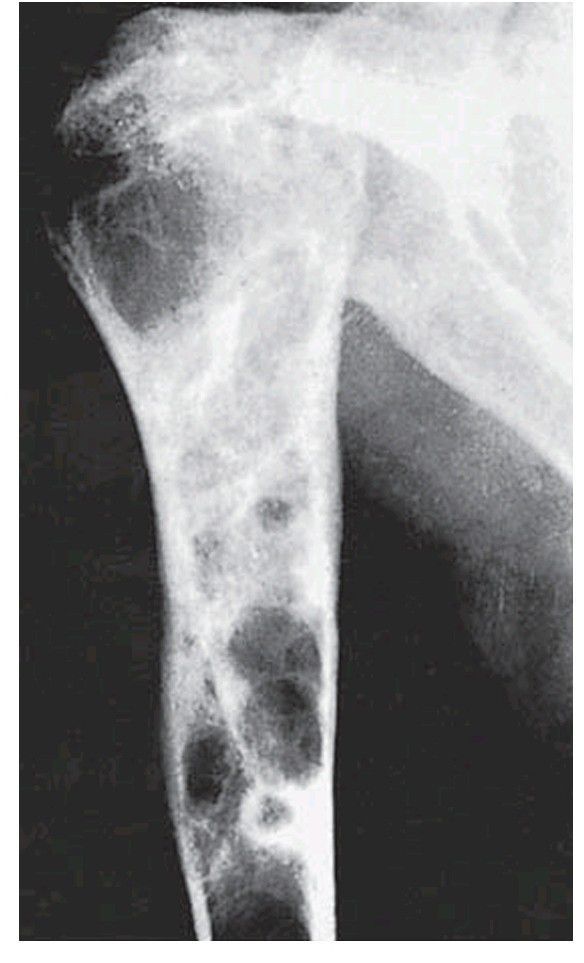

. Osteitis fi brosa cystica in the humerus of the same patient with a parathyroid adenoma. Note also the loss of trabecular pattern and cortex.